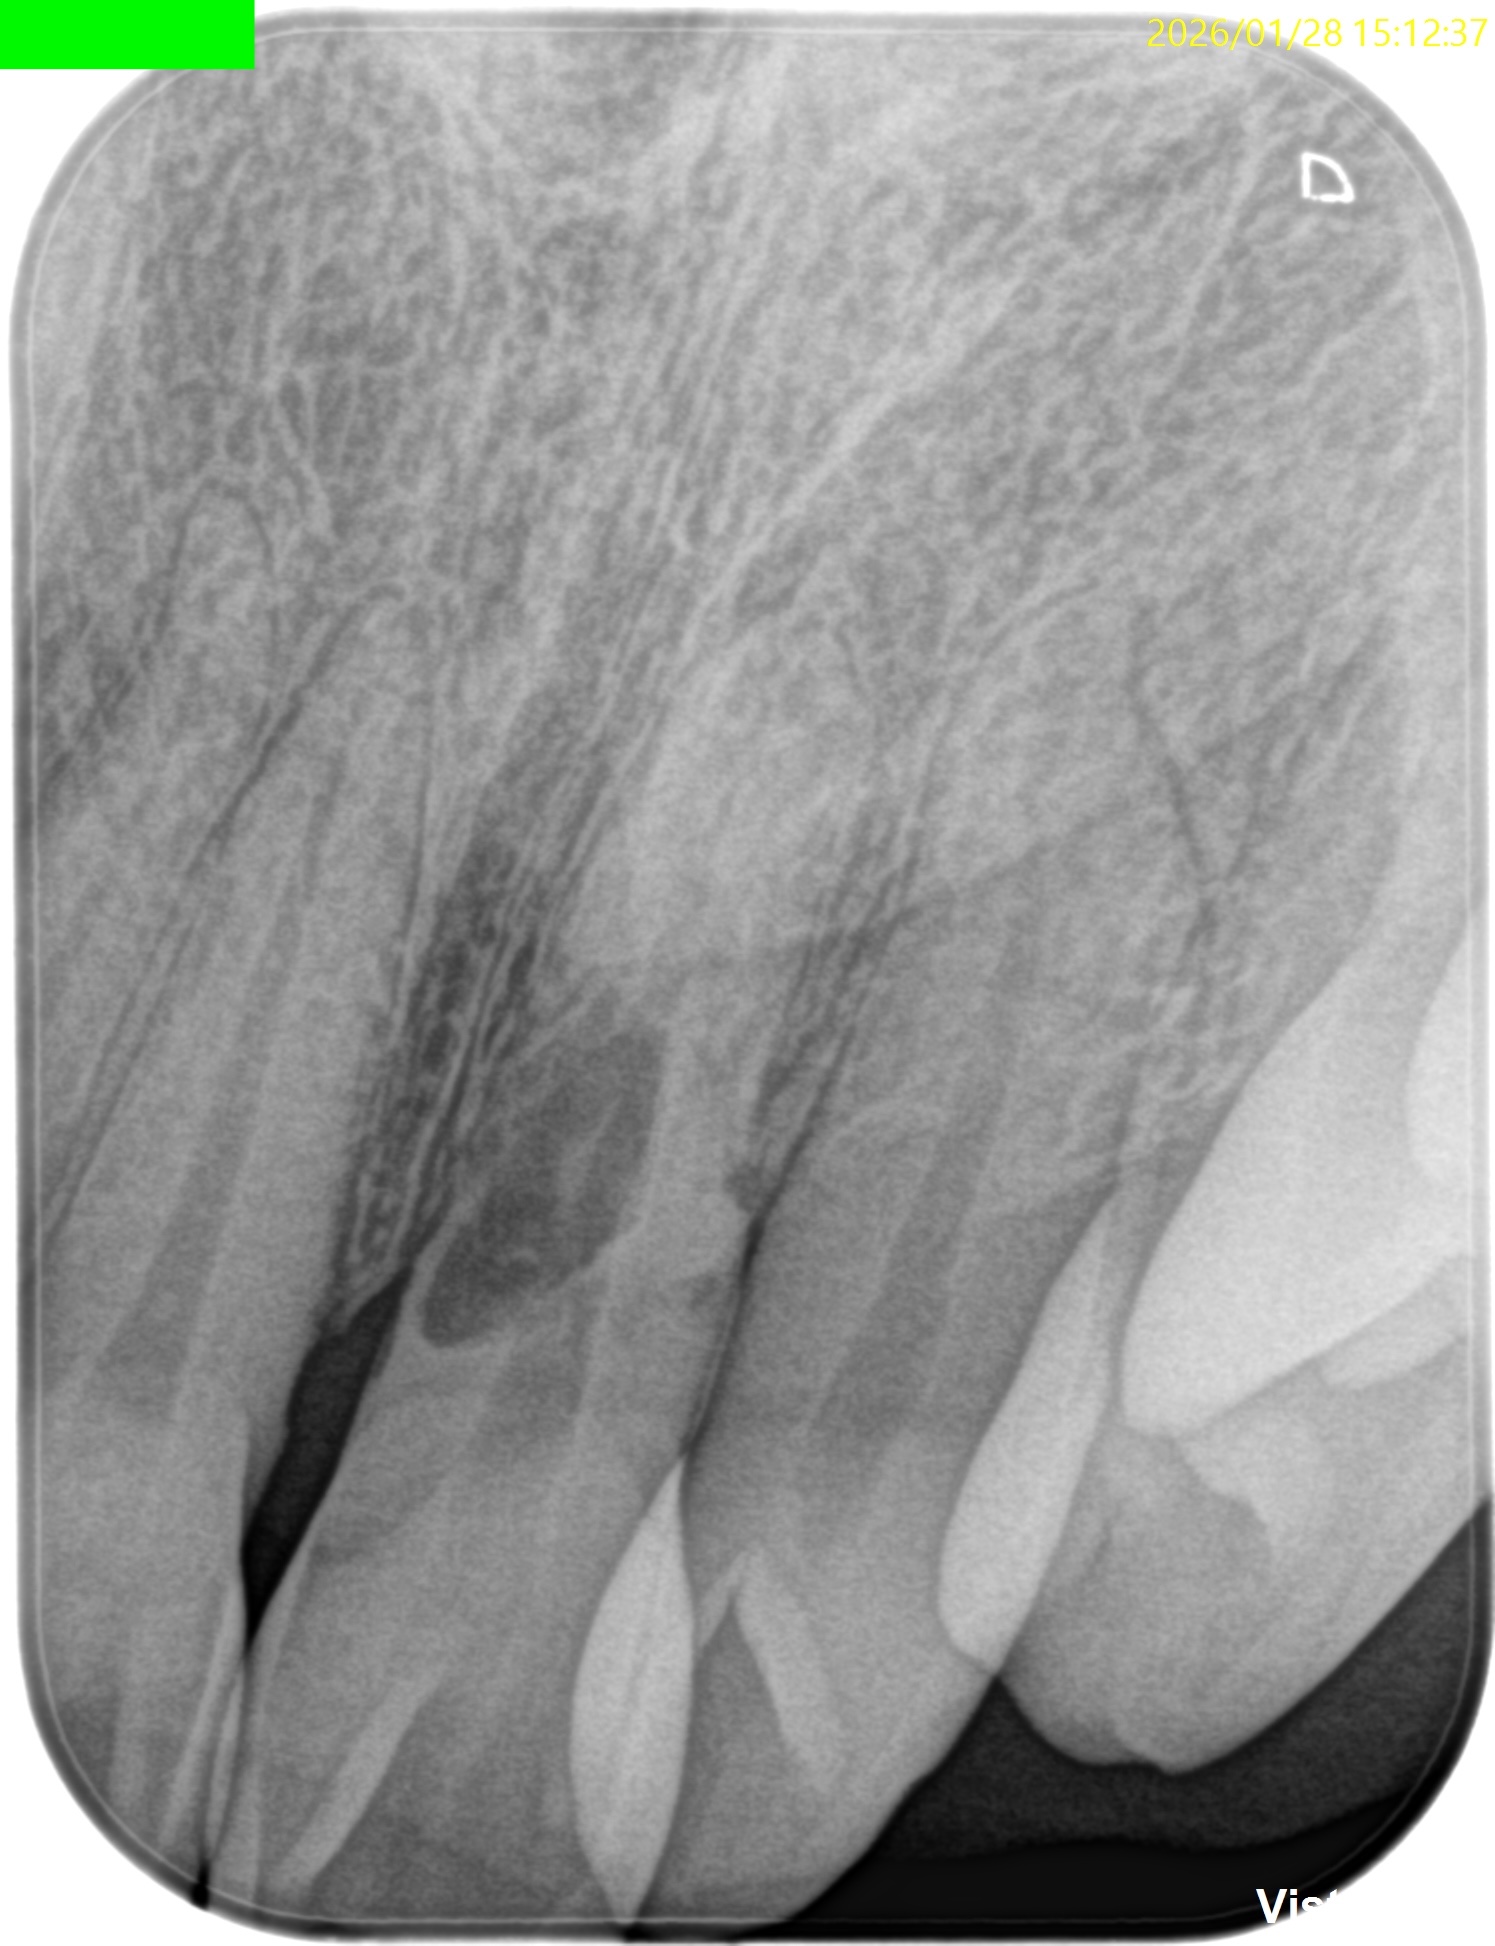

また、CBCTによればそのRIL(Radiographic Instrumentation Length)は23.4mmであるということがわかる。

そこから1mm引いた22.4mm程度が作業長だろう。

このことからもCBCTがなくては治療計画も立てられないということわかるだろう。